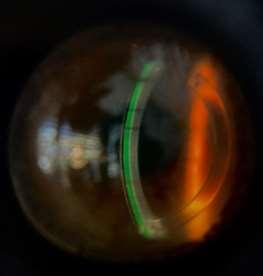

La evaluación biomicroscópica del lente mini escleral OneFit, revela una disminución del clearance especialmente inferior-, y genera un peligroso acercamiento al anillo implantado que puede afectar la comodidad y la fisiología corneal. Para corregir esto, se reduce la curva base para aumentar la profundidad de la bóveda sagital en 200 micras, y se opta por un perfil oblato del ápice del lente para acercar su cara posterior al centro corneal, con lo que se reduce el clearance central en esta zona, se provee mayor comodidad, y se minimiza la sobrecorrección negativa por compensación del menisco lagrimal; una vez transcurrido el tiempo de asentamiento del lente se procedió a evaluar la sobrerrefracción final y la zona periférica, como sigue a continuación:

Figura 14. Aspecto de la adaptación de lentes minisclerales OneFittras unahora de usocontinuo, en vista lateral del ojo derecho e izquierdo en forma respectiva.

La cronología del lente de prueba mini escleral inició después de la primera hora de uso, y se centró específicamente en la observación de cambios en el clearance, zona media limbal y zona de apoyo; el lente se mantuvo puesto por una hora adicional -completando dos en total-, y se evaluaron de nuevo los mismos parámetros para finalmente aplicar los ajustes paramétricos que se consideraron necesarios para la adaptación final, como se indica a continuación: En el ojo derecho se aumentó la altura sagital de la bóveda en 100 micras y se seleccionó el diseño oblato para reducir el clearance en la zona central; en la zona media limbal y limbal no se aplicaron cambios; mientras que en la zona de apoyo se estrecharon los bordes para lograr mejor zona de aterrizaje. En el ojo izquierdo se redujeron 50 micras al clearance; la zona media limbal y limbal no experimentó cambios; mientras que en la zona de apoyo se estrecharon los bordes para mejorar su zona de aterrizaje; en cuanto a la sobre refracción y agudeza visual resultante tras el periodo de prueba adaptativa de los lentes esclerales puestos, se lograron los siguientes valores: